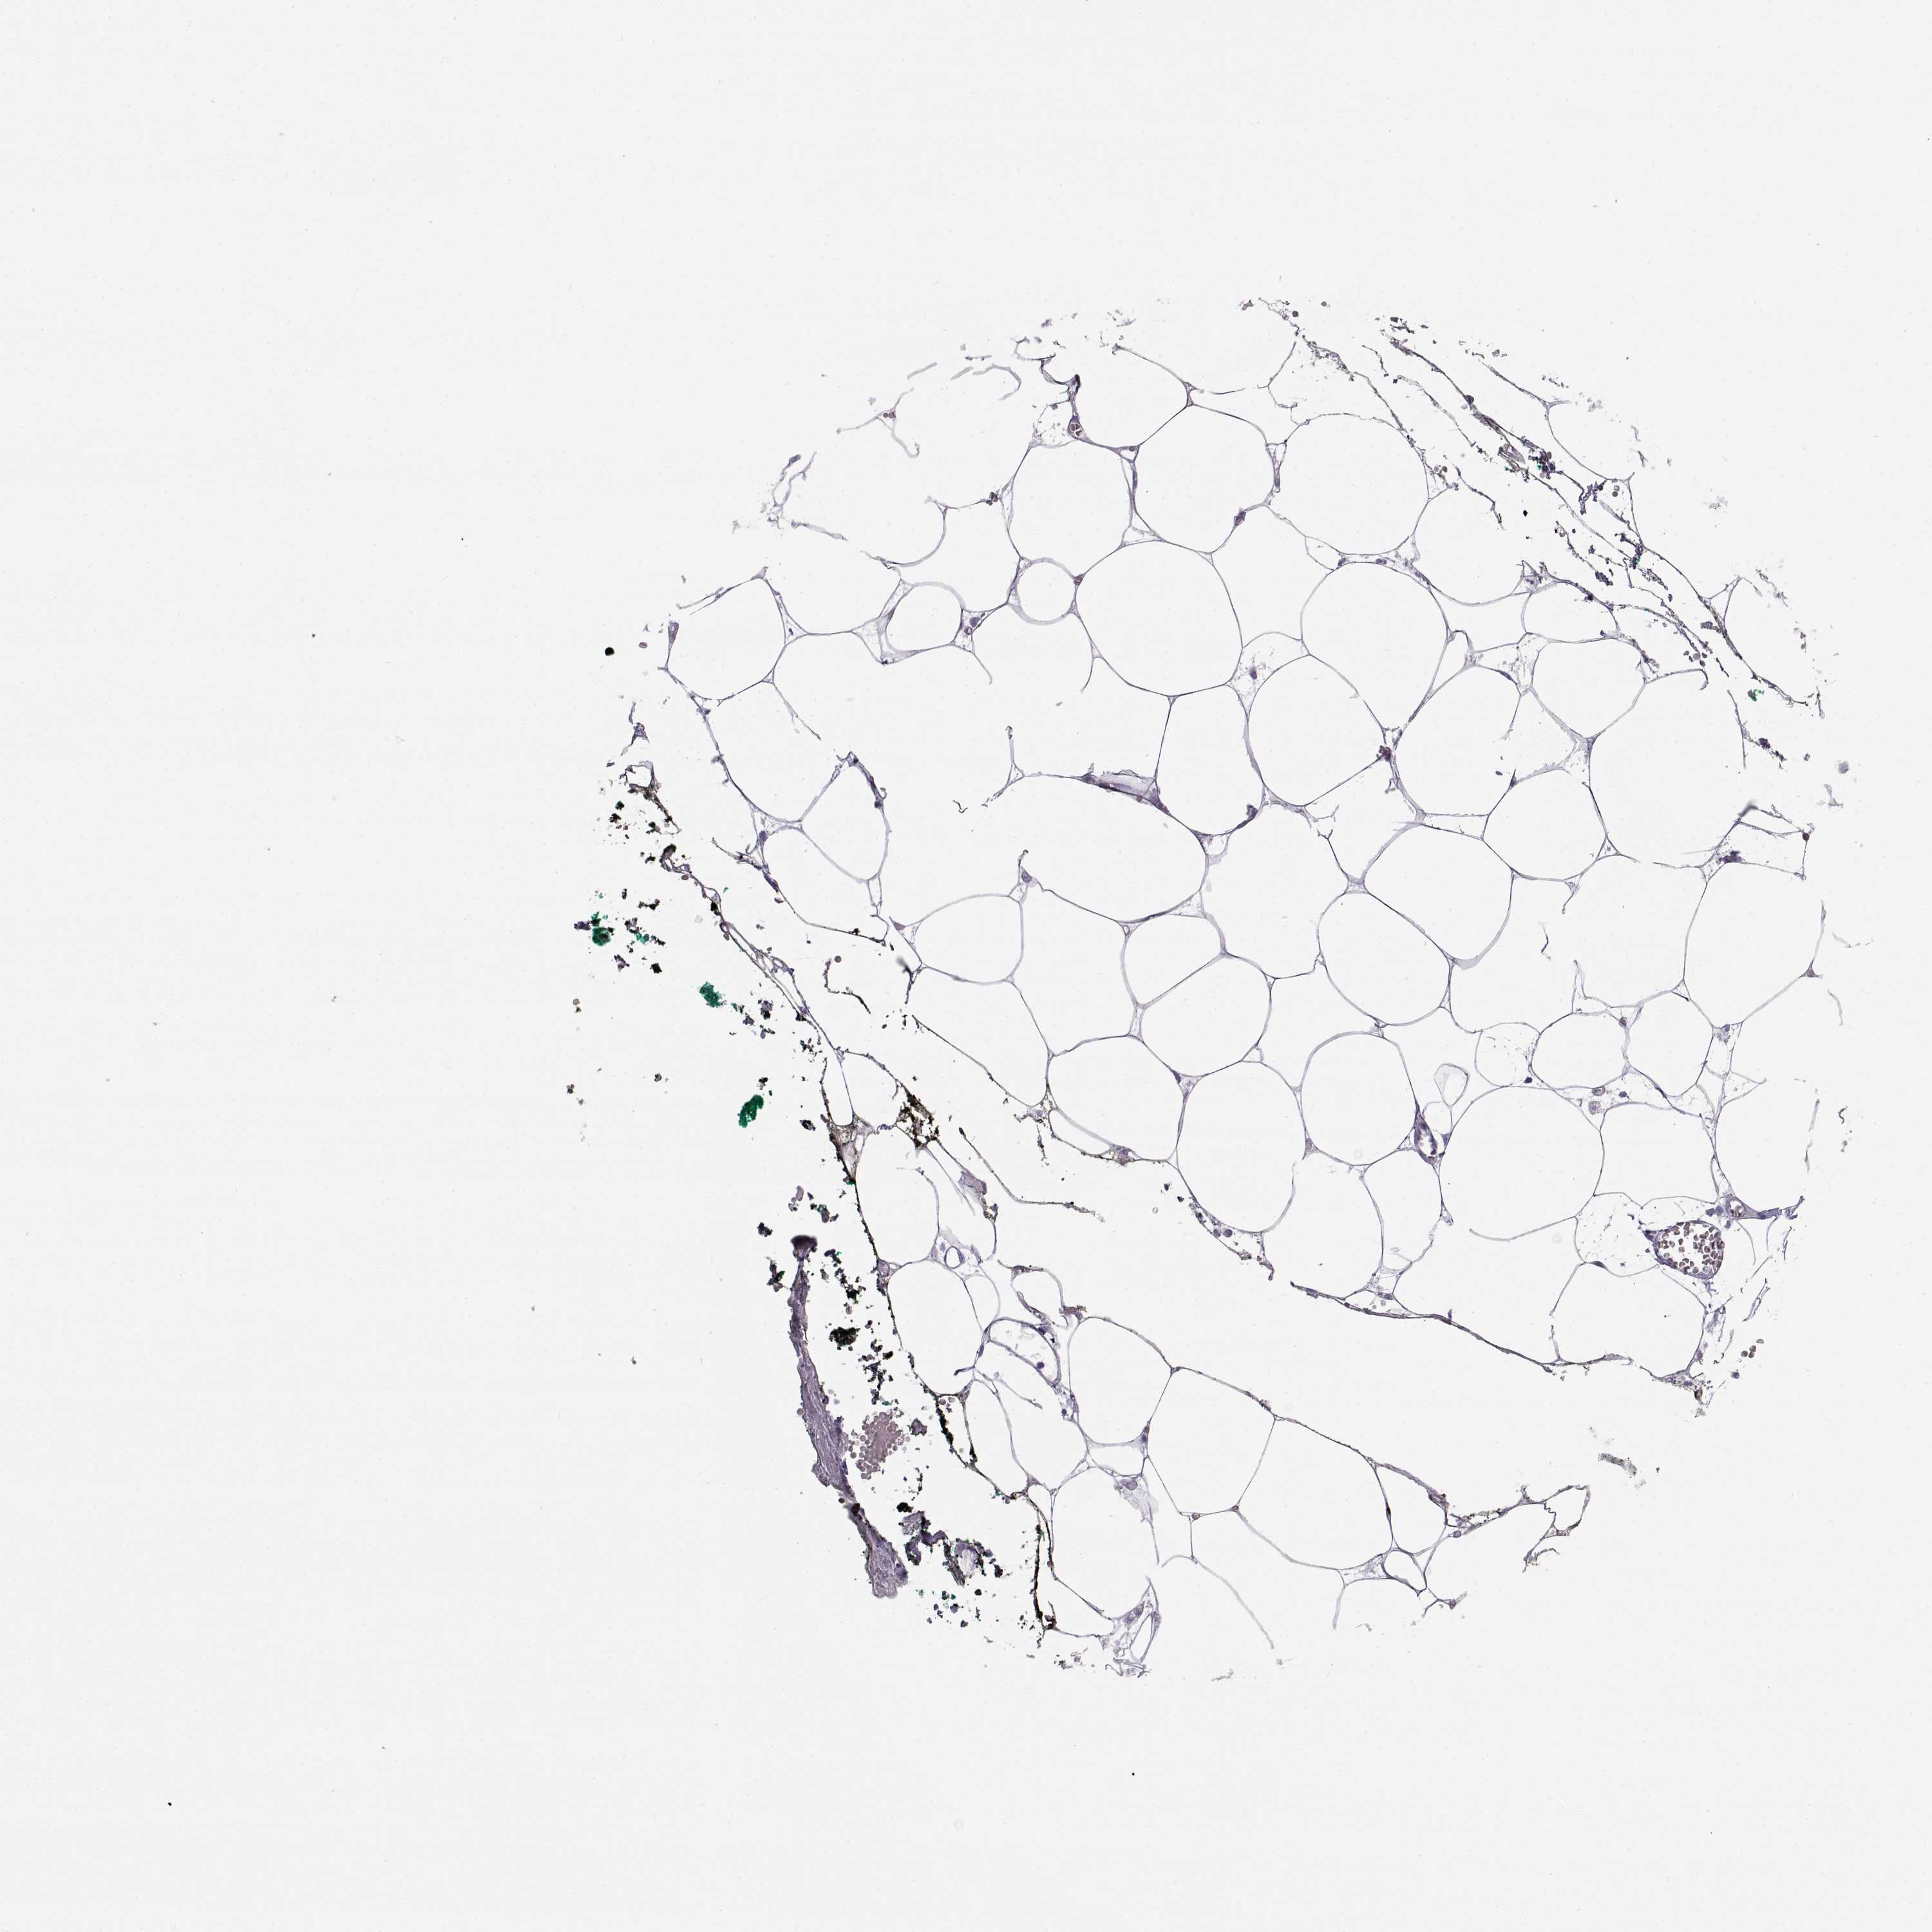

ADIPOSE TISSUE - Antibody stainingi

Antibody staining in the annotated cell types in the current human tissue is reported as not detected, low, medium, or high, based on conventional immunohistochemistry profiling in selected tissues. This score is based on the combination of the staining intensity and fraction of stained cells.

Each image is clickable and will lead to virtual microscopy that enables deeper exploration of all samples and also displays staining intensity scores, fraction scores and subcellular localization as well as patient and tissue information for each sample.

Antibody HPA042476Antibody HPA064892

Adipocytes Not detectedNot detected